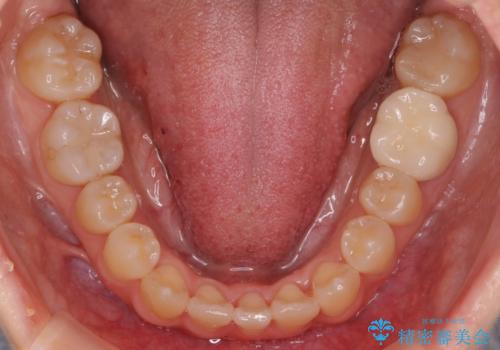

八重歯をインビザラインで 抜歯矯正

- 八重歯を主訴に来院。

出来るだけワイヤー矯正を避け、抜歯も最小限の本数をご希望でした。

下の前歯のみ1本抜歯しています。

下の前歯の周りの骨は薄いことが多く、無理に並べると唇側の骨がやせて歯ぐきが下がり歯が長く見えます。

それを回避するために今回は下顎前歯を一本抜歯をしています。